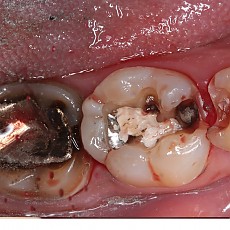

시술전후사진 12 페이지

Total 189건 12 페이지